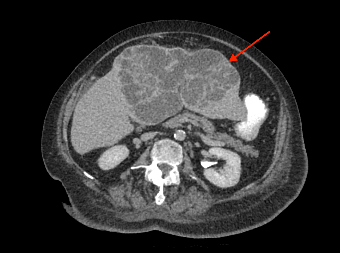

Patient had a complicated in-hospital stay which was further complicated by septic shock secondary to hospital acquired pneumonia and pericardial effusion. A repeat ultrasound liver three weeks later demonstrated a decrease in the size of the liver lesions, suggested that they favour abscess rather than metastasis. Repeat CT abdomen again confirmed the findings and also noted lobulated mucosal thickening at ileocaecal junction, suggestive of colonic neoplasm. Caecal mass was also identified in the initial CT retrospectively, which was missed initially. Colonoscopy confirmed a non-obstructing, non-circumferential mass in the caecum. Histology showed adenocarcinoma. Her liver abscess completely resolved with long course intravenous antibiotics. CT staging did not show any evidence of distant metastasis (See figure 2). An elective uncomplicated laparoscopic right hemicolectomy was performed, and she was subsequently discharged home well day six post op. Histology returned to show pT2N0M0 adenocarcinoma.

Figure 2: (a, b) Red arrow - Interval CT 2 months later illustrated significant reduction in liver mass in keeping with resolving abscesses. (b, c) Yellow arrow - Large polypoid lesion within the caecum at the ileocaecal region in keeping with carcinoma